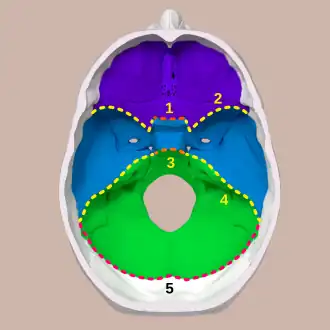

Three cranial fossae and its boundaries. Purple: Anterior cranial fossa

Blue: Middle cranial fossa

Green: Posterior cranial fossa

A cranial fossa is formed by the floor of the cranial cavity.

There are three distinct cranial fossae:[1]

- Anterior cranial fossa (fossa cranii anterior), housing the projecting frontal lobes of the brain[2]

- Middle cranial fossa (fossa cranii media), separated from the posterior fossa by the clivus and the petrous crest housing the temporal lobe[3]

- Posterior cranial fossa (fossa cranii posterior), between the foramen magnum and tentorium cerebelli, containing the brainstem and cerebellum[4]